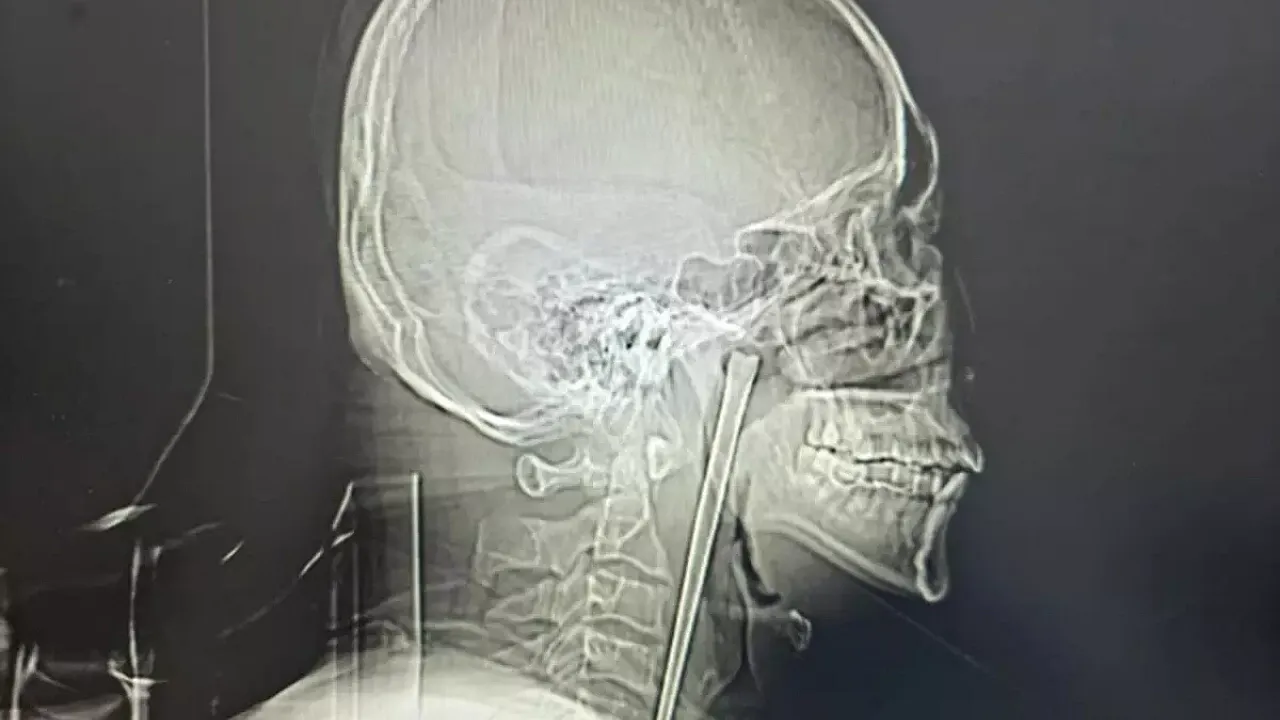

• Şiddetli boğaz ağrısı şikayetiyle hastaneye giden hastanın röntgeninde, hayati damarların hemen yanına yerleşmiş dev bir metal cisim tespit edildi.

Aradan geçen yıllar boyunca boğazındaki yabancı cisim hissini "katlanılabilir" bulan Wang, son dönemde şiddetli ağrıların başlamasıyla Dalian Üniversitesi Teknoloji Hastanesi’ne başvurdu. Yapılan ilk fiziki muayenede herhangi bir enfeksiyon izine rastlanmasa da çekilen röntgen filmi korkunç gerçeği ortaya çıkardı: Boğaz dokusunun iç kısımlarına yerleşmiş, hayati damarların hemen yanında duran 12 santimetrelik dev bir metal şaft.